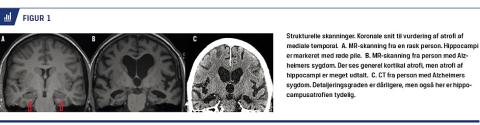

PET med anvendelse af sporstoffer, som bindes til AS-specifik patologi har vundet større udbredelse i de senere år. Fra 2008 har man anvendt PET med betaamyloidsporstoffet Pittsburgh compound B (PiB) i Danmark. Fordelen ved at påvise betaamyloid med PET frem for i CSV er, at PET oftest giver et enten-eller-signal (Figur 3), hvor betaamyloid i CSV kan variere som følge af prøvetagningsprocedurer og assay-variation. Der er dog ganske god overensstemmelse mellem de to metoder med ca. 85% konkordans [8]. PET-PiB synes umiddelbart at være CSV overlegen, når det gælder påvisning af betaamyloid [8], men især omkostninger og logistik begrænser anvendelsen. PET-amyloidskanning øger den diagnostiske sikkerhed og antallet af patienter, som får korrekt behandling, især hos personer med usikker diagnose [9-11]. Metoden kan således anbefales hos diagnostisk uafklarede patienter med kognitiv dysfunktion, hvor påvisning af AS-patologi får en afgørende betydning for information, rådgivning og behandling [12]. Man kan med stor sikkerhed afklare, om patienter har betaamyloid i hjernen ved en simpel visuel bedømmelse af PET-amyloidskanninger (sensitivitet og specificitet hhv. 98% og 89% [13]), men man skal være opmærksom på, at betaamyloidophobning i hjernen forekommer med stigende hyppighed med alderen hos kognitivt raske personer.